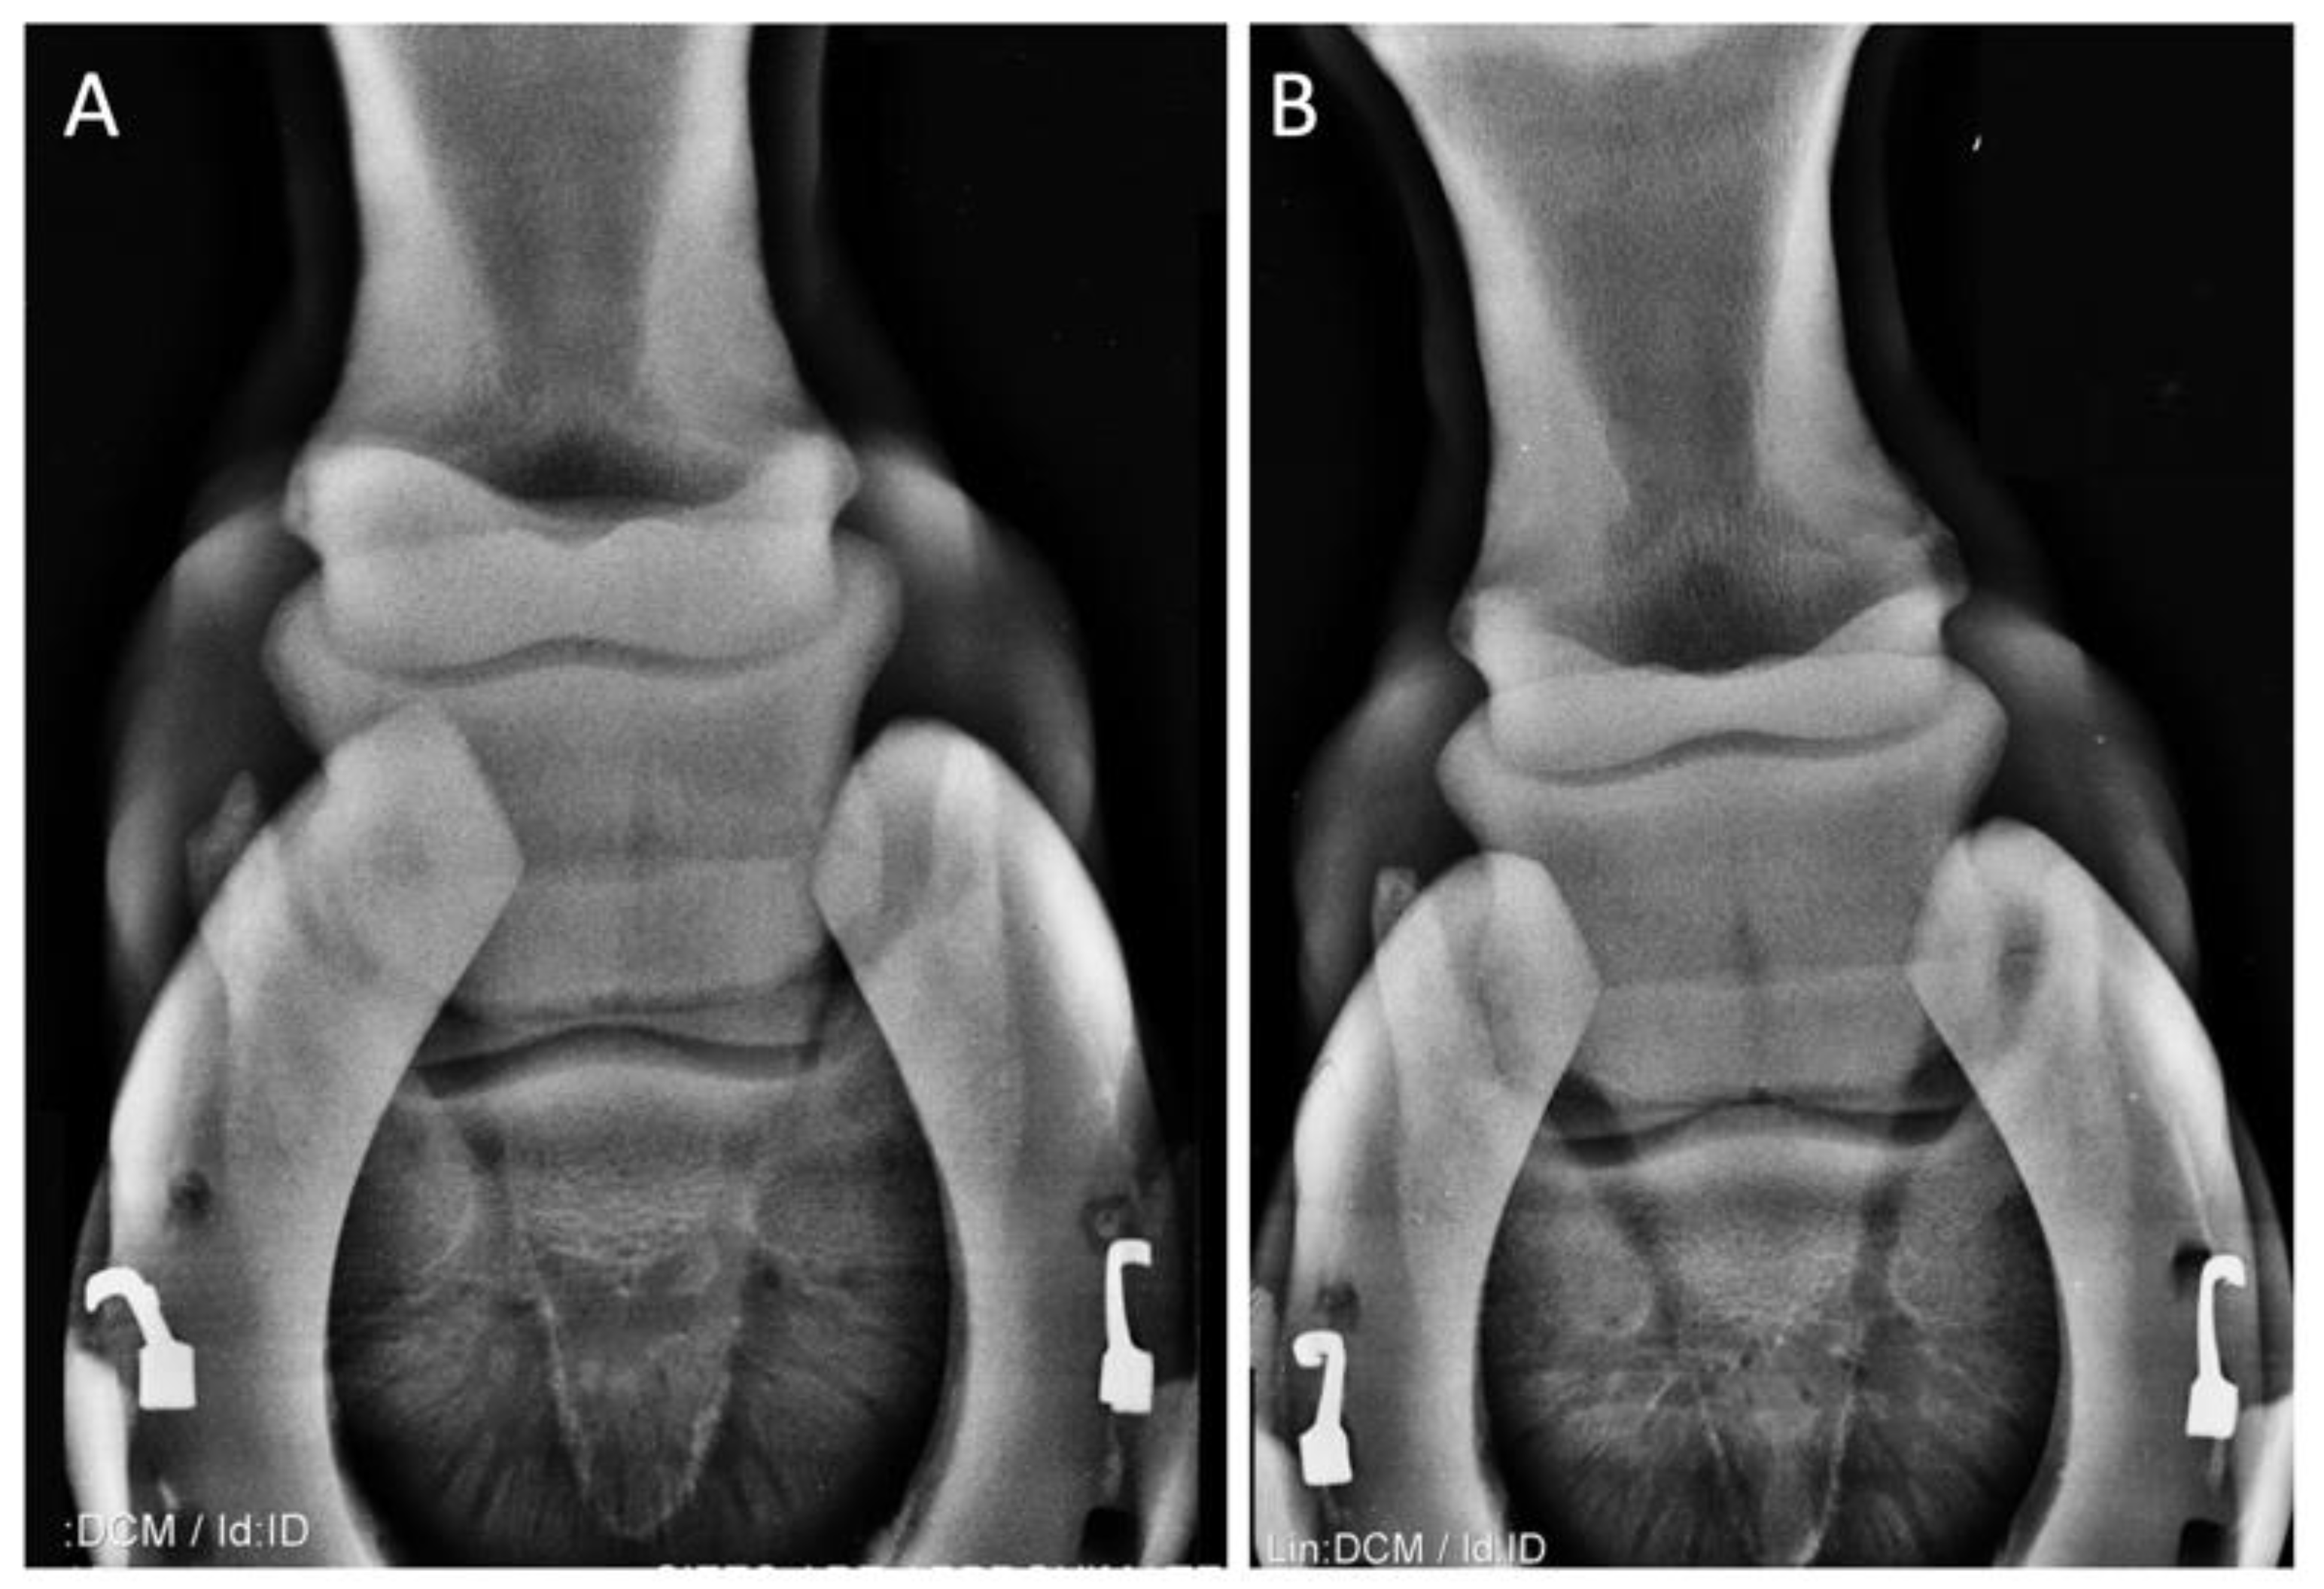

| (1) 7-year-old S.I. gelding jumping horse | Navicular sindrome | Lameness Flexion test | 1 3 | 1 2 | 0 1 | 0 0 | 0 0 |

| (2) 16-year-old NRPS gelding jumping horse | Navicular syndrome and distal interphalangeal joint arthrosis of the right anterior limb | Lameness Flexion test | 3 3 | 2 3 | 2 2 | 1 1 | 0 0 |